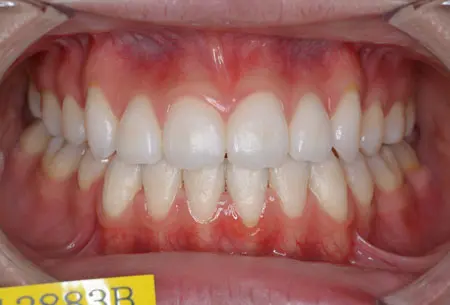

2024.08.1720代女性「出っ歯と歯のガタガタが気になる」叢生を伴う上顎前突症をワイヤー矯正で治療した症例